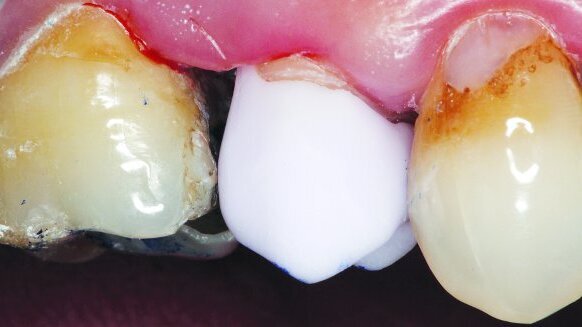

A 53-year-old male patient presented after undergoing recent endodontic treatment on tooth #13 (Fig. 1) and was unhappy with the tooth’s appearance. Along with decay on the adjacent dentition, tobacco stains were also present because the patient was a smoker (Fig. 2). Although the patient requested that treatment be confined to only tooth #13, after a routine head, neck and oral cavity examination, the patient was informed of multiple treatment needs and advised that a comprehensive treatment plan should be started as soon as possible.

The crown was tried in the patient’s mouth over the tooth #13 preparation to evaluate fit, contour and anatomical harmony (Figs. 7 & 8). Upon confirmation of proper fit and function, the crown was removed, cleaned and dried. Stains were then placed on the crown surface to mimic the tobacco stains on the surrounding dentition. However, it was decided that cervical stains to mimic the decay on the natural dentition would not be placed. After staining, the lithium disilicate crown was crystallised and ready for immediate seating (Fig. 9). The specialised mouthpiece (Isolite) was repositioned in the mouth to isolate the tooth during cementation.